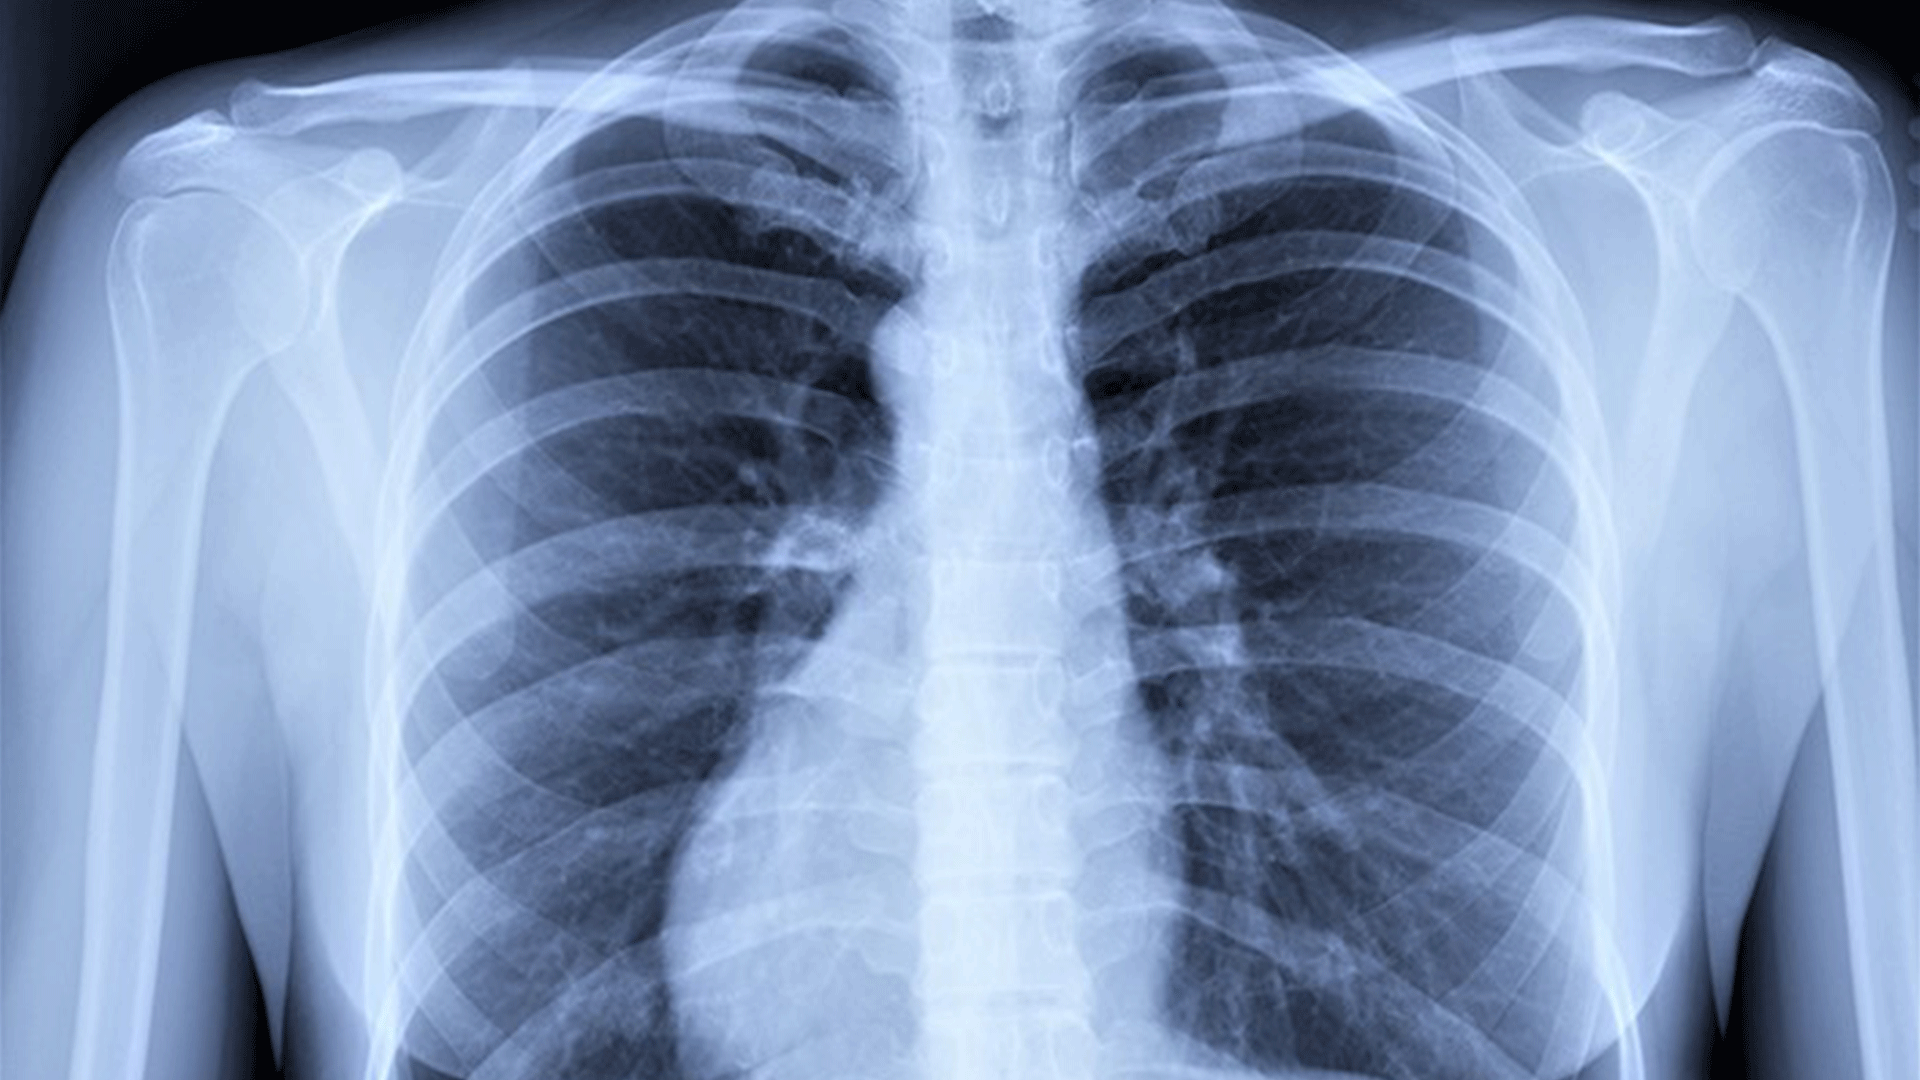

Covid Cxr Appearance